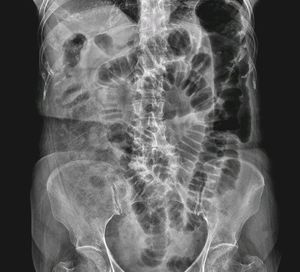

Point out the colon cutoff sign in this abdominal radiograph above in Acute Pancreatitis

Pretty cramped colon!